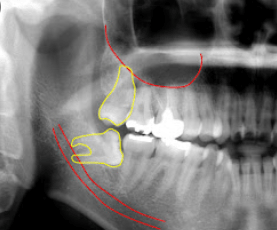

지금 제 상황과 가장 유사한 사진 인용했습니다.

좌측 아래 사랑니이고 80도 정도 누워있는데 어금니를 혀 쪽으로 밀어내어 살짝 들어갔습니다.

이런 경우에는 사랑니를 발치해 주는 것이 좋은데 사진처럼 사랑니의 뿌리가 신경과 가깝다면 발치 도중에 신경손상이 발생하는 경우가 있습니다.

첨부한 사진의 경우 매복되어 발치시 신경손상의 위험이 있으므로 큰 병원에서 발치하는걸 추천드립니다.

2. 해당 사진으로 보면 사랑니가 부분매복되어 있는 경우이며, 이런 경우에는 두번째 큰어금니와 사랑니 사이 공간으로 음식물 등의 이물질이 쉽게 끼어들어가지만 빼내기 힘든 부위입니다.

3. 이런 이유로 위 사진과 같은 경우라면 사랑니가 아닌, 앞 어금니가 손상될 가능성이 높기 때문에 예방적으로 사랑니를 뽑는 것이 권장됩니다.